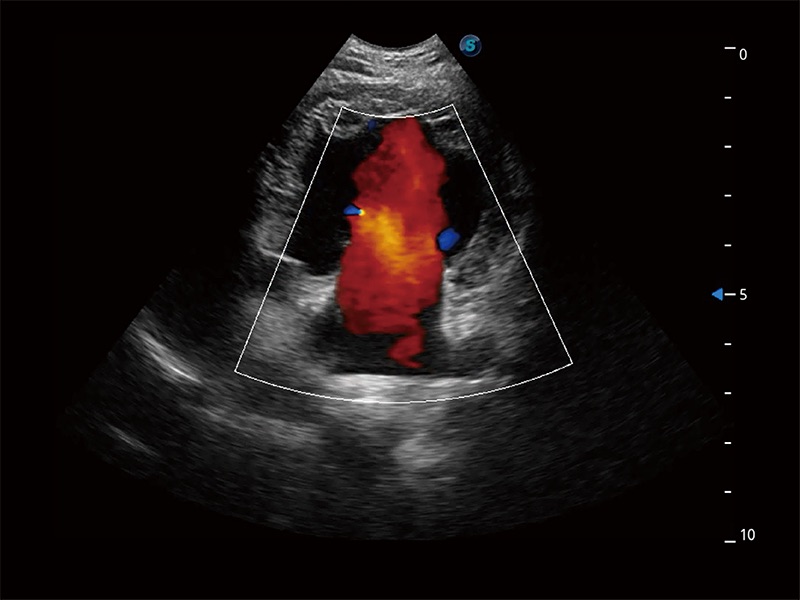

极大提升超低速微细血流的检出能力,同时更精准地滤除软组织和超声信号,为兽用医生提供以往无法通过常规血流获得的疾病诊断信息。

在传统二维血流成像的基础上,呈现血流的立体感,具有动感的生命力之美。即便是微小的血管也能轻松应对,提高了血流的视觉敏感性。

ProPet 80 配备了丰富的心脏探头群、先进的成像技术和专业的心脏测量工具,可帮助动物医生为不同体型和生理结构的动物提供心脏和心肌功能的全面评估。